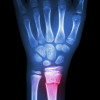

Fraktur radius distal merupakan salah satu fraktur ekstremitas atas yang paling sering terjadi, terutama pada populasi lansia dan penderita osteoporosis. Sekitar 1 dari 5 fraktur pada populasi lansia adalah fraktur radius distal.[1,2]

Fraktur radius distal dapat ditangani secara konservatif ataupun secara bedah sesuai dengan penilaian klinis dan penilaian radiografis masing-masing kasus. Pasien dapat diimobilisasi dengan atau tanpa reduksi (dengan pemasangan gips saja) atau dioperasi dengan metode fiksasi internal atau eksternal.[1,2]